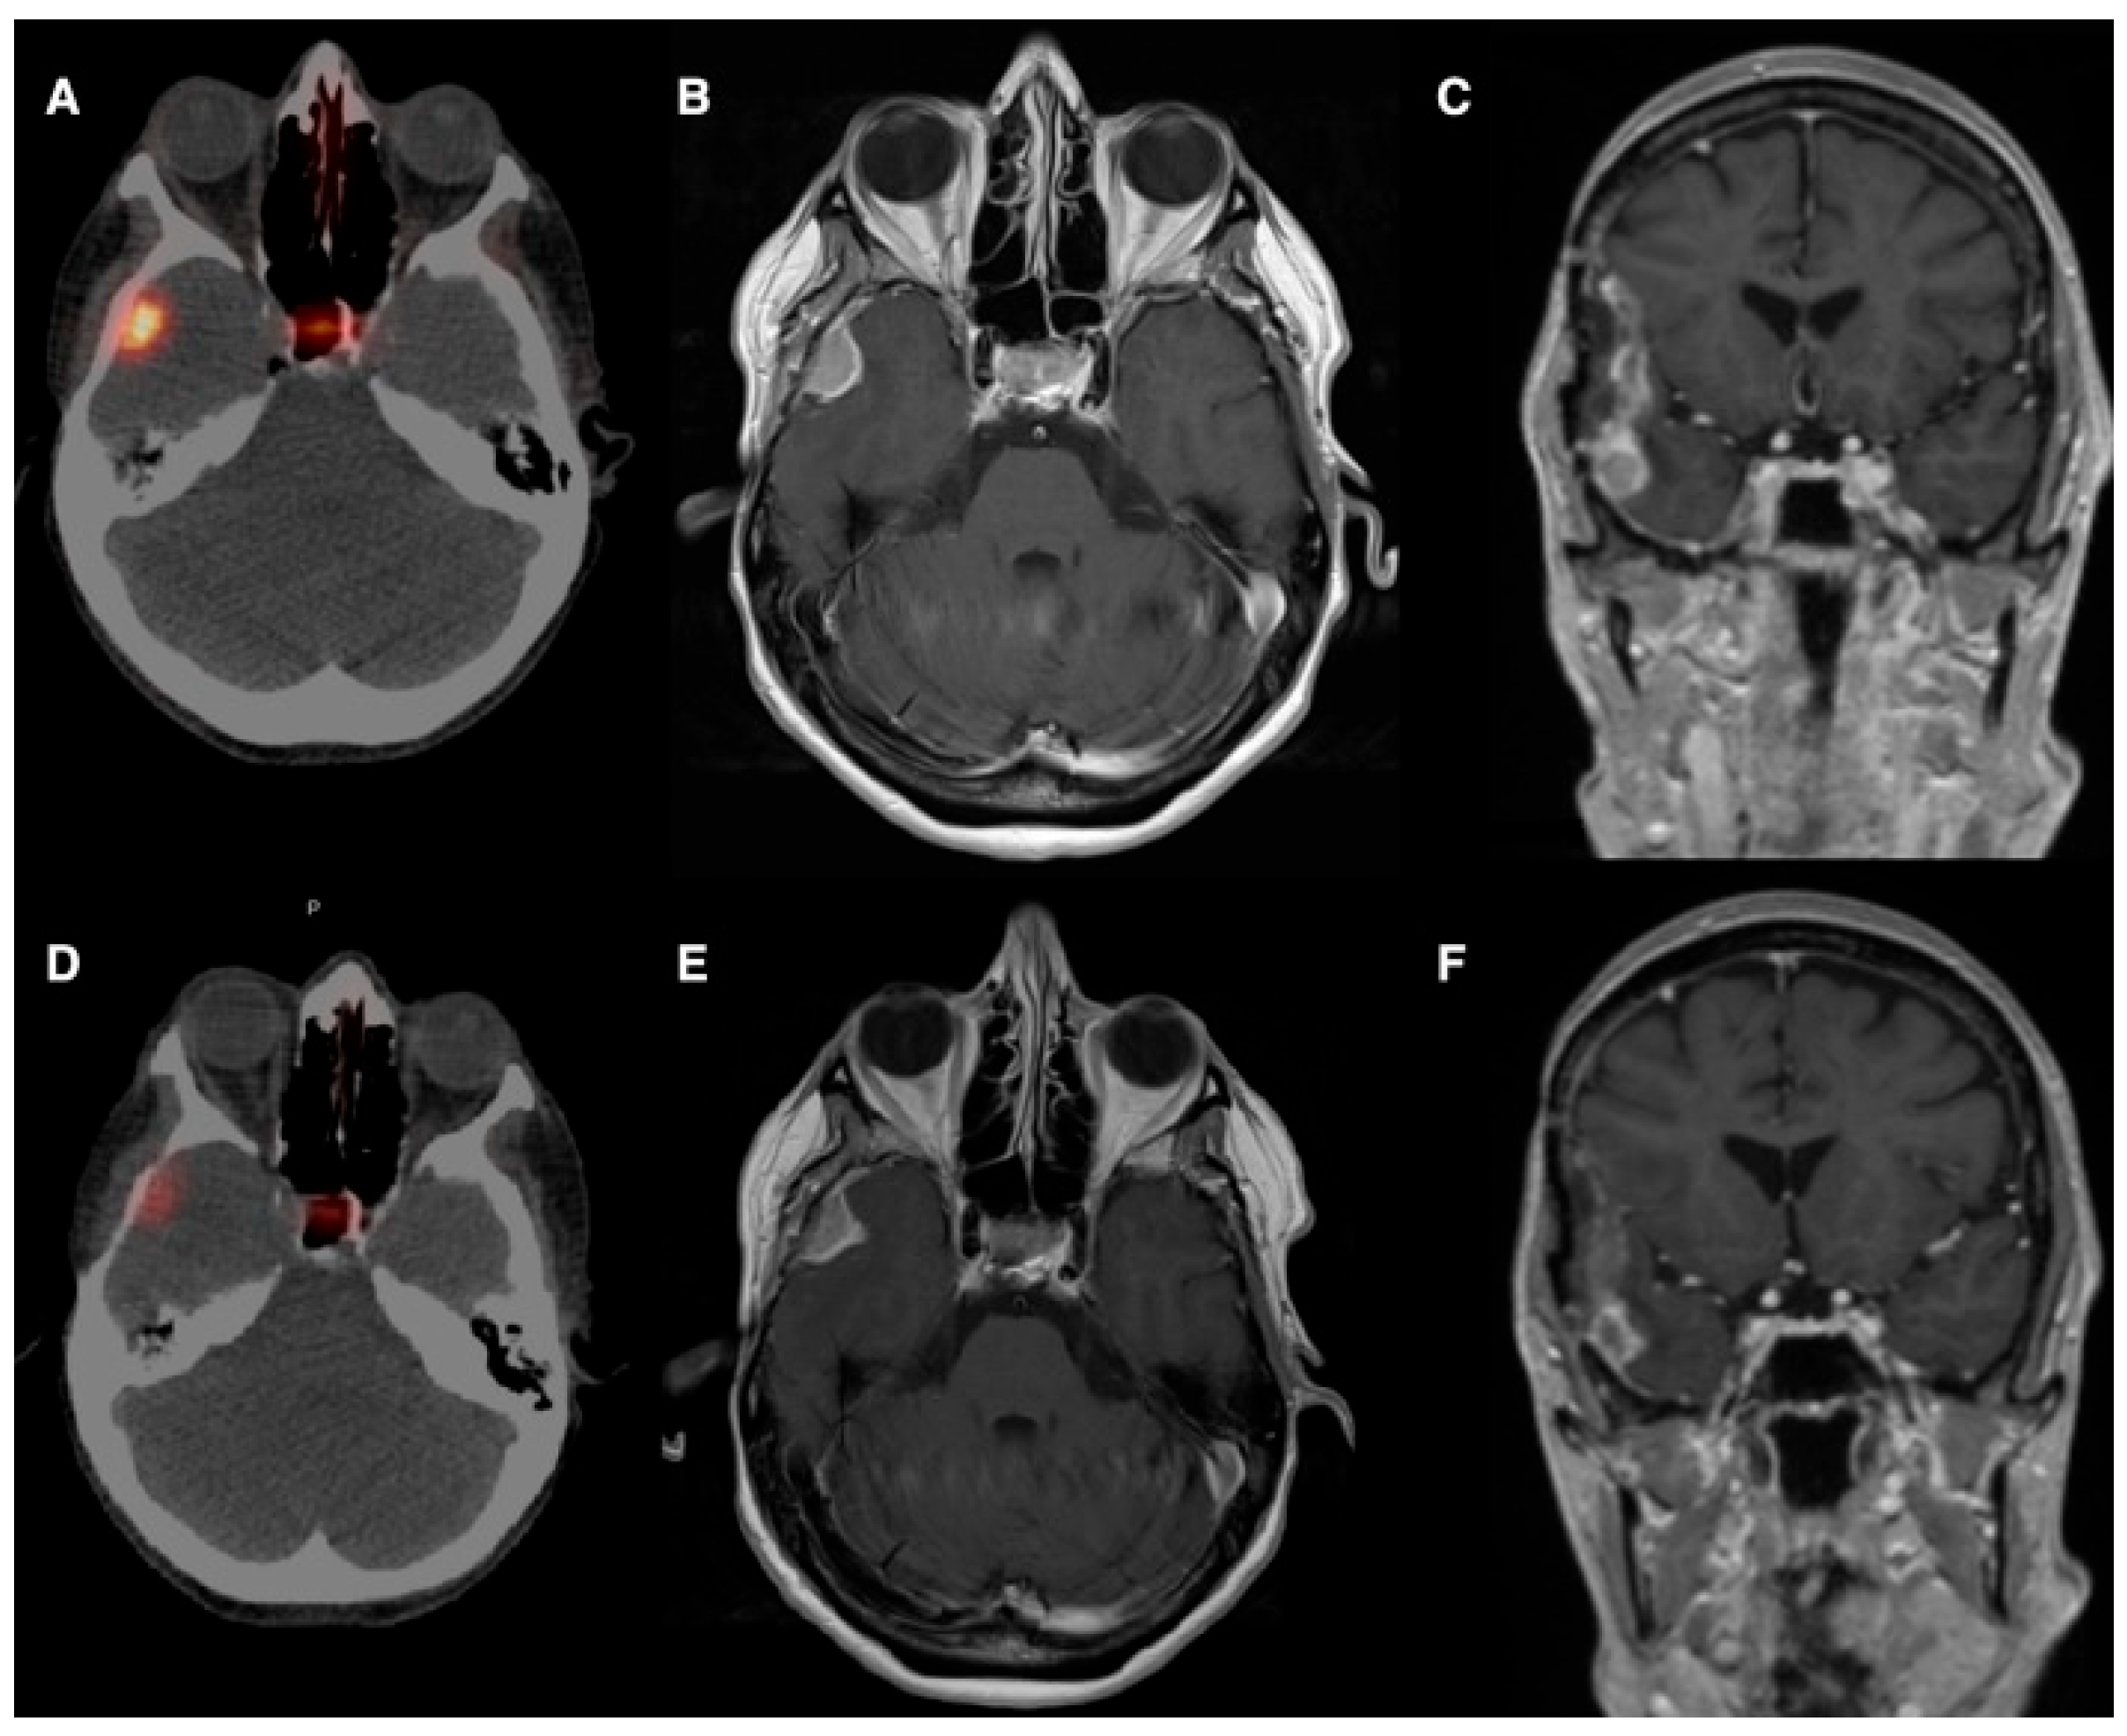

The first experience by Braat et al. [19] provided the rationale for selective vascular delivery in meningioma. They reported the case of a 54-year-old woman with a recurrent right-temporal WHO grade II meningioma, refractory to three surgical resections and seven courses of radiotherapy, presenting with frequent focal seizures and recurrent status epilepticus. As the tumor was deemed unresectable and further external radiotherapy unsafe, 68Ga-DOTATOC PET/CT demonstrated high SSTR2 expression, prompting treatment with PRRT. An initial intravenous administration of 7.4 GBq 177Lu-DOTATATE resulted in low tumor uptake and an estimated absorbed dose of approximately 4.6 Gy. Subsequently, selective IA administration via the right external carotid artery led to an 11-fold increase in tumor uptake, achieving an estimated absorbed dose of 51 Gy per cycle. After four PRRT cycles (one intravenous and three IA; cumulative activity 29.6 GBq), the estimated total tumor absorbed dose reached 154 Gy. Follow-up PET/CT and MRI demonstrated a marked reduction in SSTR2 expression, central tumor necrosis, and a partial radiological response. Clinically, severe seizures resolved completely, while focal sensory seizures decreased from daily episodes to 3–4 per week, with stable control and sustained partial response at 10-month follow-up and no relevant treatment-related toxicity (Figure 2 and Figure 3).

Figure 2. (A). Baseline 68Ga-DOTATOC PET/CT shows high SSTR expression in the right-temporal meningioma and normal pituitary uptake. (B,C). Gadolinium-enhanced T1 MRI shows a uniformly enhancing solid lesion. (D). Post-treatment gallium-68-DOTATOC PET/CT shows a 79% decrease in SSTR2 expression. (E,F). Post-treatment T1 MRI shows a partial response with a 38% volume and 24% diameter reduction, central necrosis, and reduced enhancement in the prior resection cavity. Reprinted from [19] under a creative commons attribution 4.0 international license (http://creativecommons.org/licenses/by/4.0/, accessed on 31 October 2025). No changes were made.